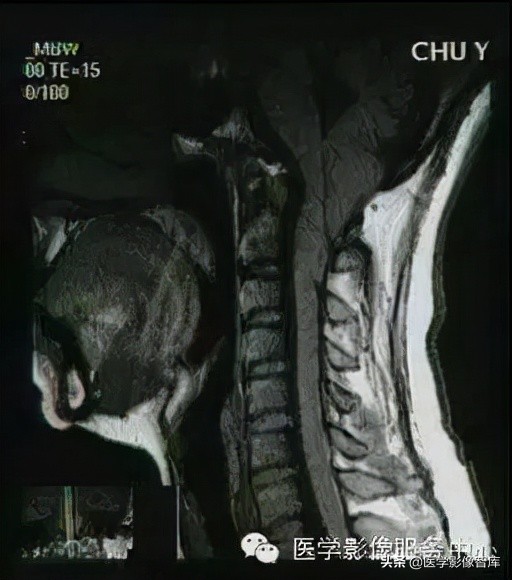

Chiari 畸形 又称小脑扁桃体下疝畸形,是后脑的先天性畸形。 Chiari 畸形的根本原因 是由于后颅窝先天发育不良、容积小而使小脑扁桃体下部疝入到枕骨大孔所致。 其病理特点 是小脑扁桃体下部疝入到椎管内,桥脑、延髓和第四脑室延长、扭曲,并向椎管内移位。此畸形大约56%伴有脊髓空洞畸形。

Chiari畸形 I 型 Chiari 畸形 I 型常较多见。 主要病理改变 为小脑扁桃体与小脑下蚓部向下疝入椎管。 诊断标准: 小脑扁桃体下端疝出枕骨大孔平面5mm以上。患者常合并脊髓空洞和轻度脑积水。

Chiari畸形 Ⅱ型 Chiari畸形 Ⅱ型为最常见的类型。 病理改变: 在I型的基础上延髓、脑桥下部向下移位,第四脑室下移延长。大多数患者合并脊髓脊膜膨出,几乎所有患者均合并脊髓空洞和脑积水,本型尚可合并颅内其他畸形。